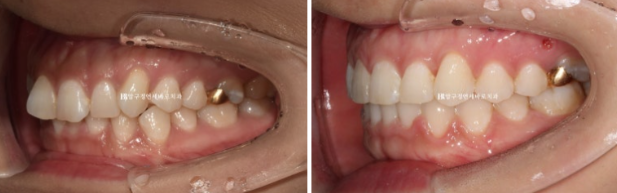

23.04~24.10

원래 좋았던 어금니 교합은 잘 유지가 되었습니다.

앞니 돌출은 해소가 되었고

배열도 가지런해졌습니다.

위 앞니 두 개가 사이즈가 커서 미량의 치간삭제로 치아 옆면 모양을 다듬어 미적인 완성도를 높였습니다.

치간삭제 하면 치아가 약해지지 않나요?

많이 물어보십니다.

만약 환자분이 치아가 시리거나 약해지면 저희가 평생 책임을 지어야 하는데

그렇게 치간삭제를 많이 하지 않습니다.

허용된 범위 내에서 치아의 자연적 마모도 정도만 진행하면 아무 불편함 없습니다.